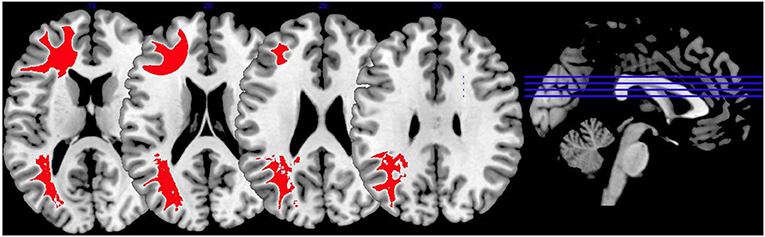

Synthesis of Findings From Studies Using Face Affect Recognition Paradigms

In Figure 3, we provide an overview on activation patterns during face affect recognition over all reviewed studies. In Figure 3A, VS show hyperactivation in the right amygdala in persons with high as opposed to low psychopathy scores when viewing facial expressions of disgust. To our knowledge, there are no previous studies on brain activation patterns of aggressive persons on disgustful faces, but it has been observed that more aggressive persons exhibit higher amygdala activation when seeing angry faces (15).

Figure 3. Face affect recognition activations. Overview of the working memory brain activation patterns reported by the reviewed studies in the group comparison VS high vs. VS low. Hyperactivations are shown in red, hypoactivations in blue. (A) Shows the activation patterns in the group comparison VS high vs. VS low with VS high>VS low in red showing the contrast of neutral vs. disgustful faces, (B) shows the activation patterns in the group comparison VS high vs. VS low with VS high<VS low in blue showing the contrast of neutral vs. fearful faces. Shown slice numbers are 100, 110, 120, 130.

When viewing fearful faces, as shown in Figure 3B, VS with high vs. low psychopathy hypoactivated the right amgydala. This is in line with findings reporting that persons with schizophrenia show hypoactivations of the amygdala in response to emotional stimuli.